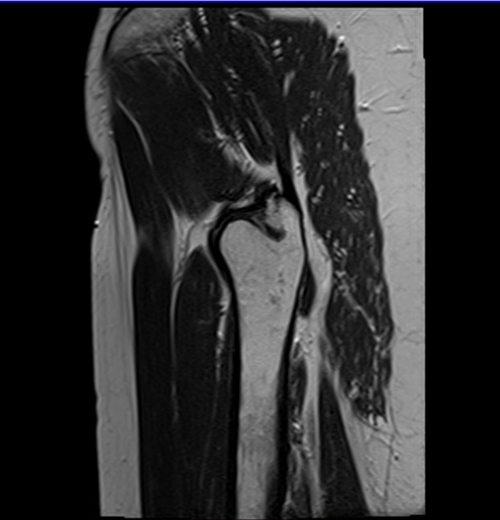

MRI hips sagittal t2 images

mri hips sagittal t2 image